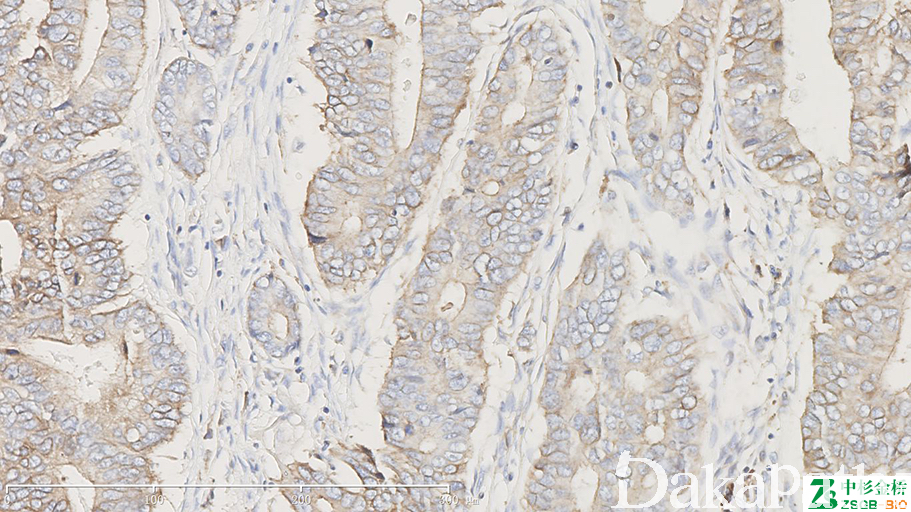

COX-2

在细胞凋亡和肿瘤发生中起一定作用,在大肠癌和乳腺癌中高表达。

信号定位: 胞质、胞膜

通常阳性(<95%,≥75%的病例阳性): 皮肤鳞状细胞癌、结直肠腺癌、肝细胞癌、甲状腺髓样癌、乳腺导管原位癌、胃肠道间质瘤、恶性嗜铬细胞瘤、乳腺浸润性癌,非特殊类型、甲状腺未分化癌、胰腺导管腺癌